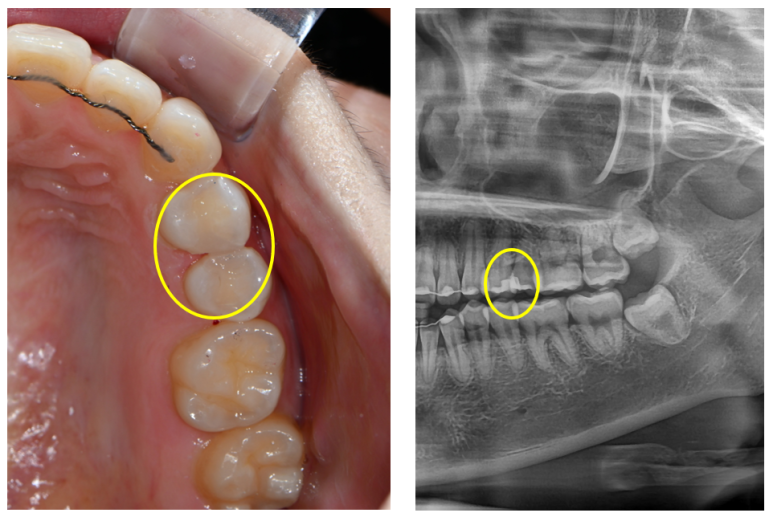

이젠 감쪽같이 치료가 마무리 되었습니다.

잘 보시면 똑같은 부위에 멍들어 보이던 치아가 이젠 깨끗이 치료된 것을 보실 수 있을거에요!

기억자와 니은자처럼 생긴 레진 인레이 두개가 예쁘게 자리잡아 있네요. 사랑니를 보기 위해 찍었던 파노라마 사진에서 확인할 수 있었답니다. 완전 깔끔 !!!